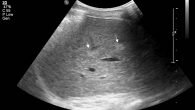

Благодаря делению органа на зоны, увеличивается шанс получения точных результатов неинвазивного метода печеночного обследования. Такие методы дают возможность осмотреть сосуды и борозды, определить место, в котором произошло нарушение, и вовремя заметить развитие опухолевых образований в органе. Центральная роль при проведении УЗИ отводится крупным сосудам и желчным протокам, которые являются ориентирами. Бывают такие формы срезов УЗИ, как подреберная, поперечная и продольная. С помощью УЗИ определяют изменение печеночного размера, развитие плохого переваривания жировых соединений, появление карцином.